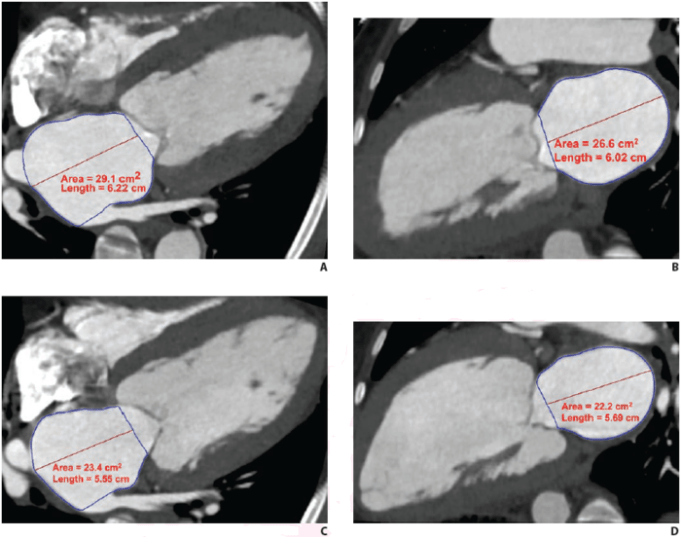

Researchers have developed a novel method of measuring growth of thoracic aortic...